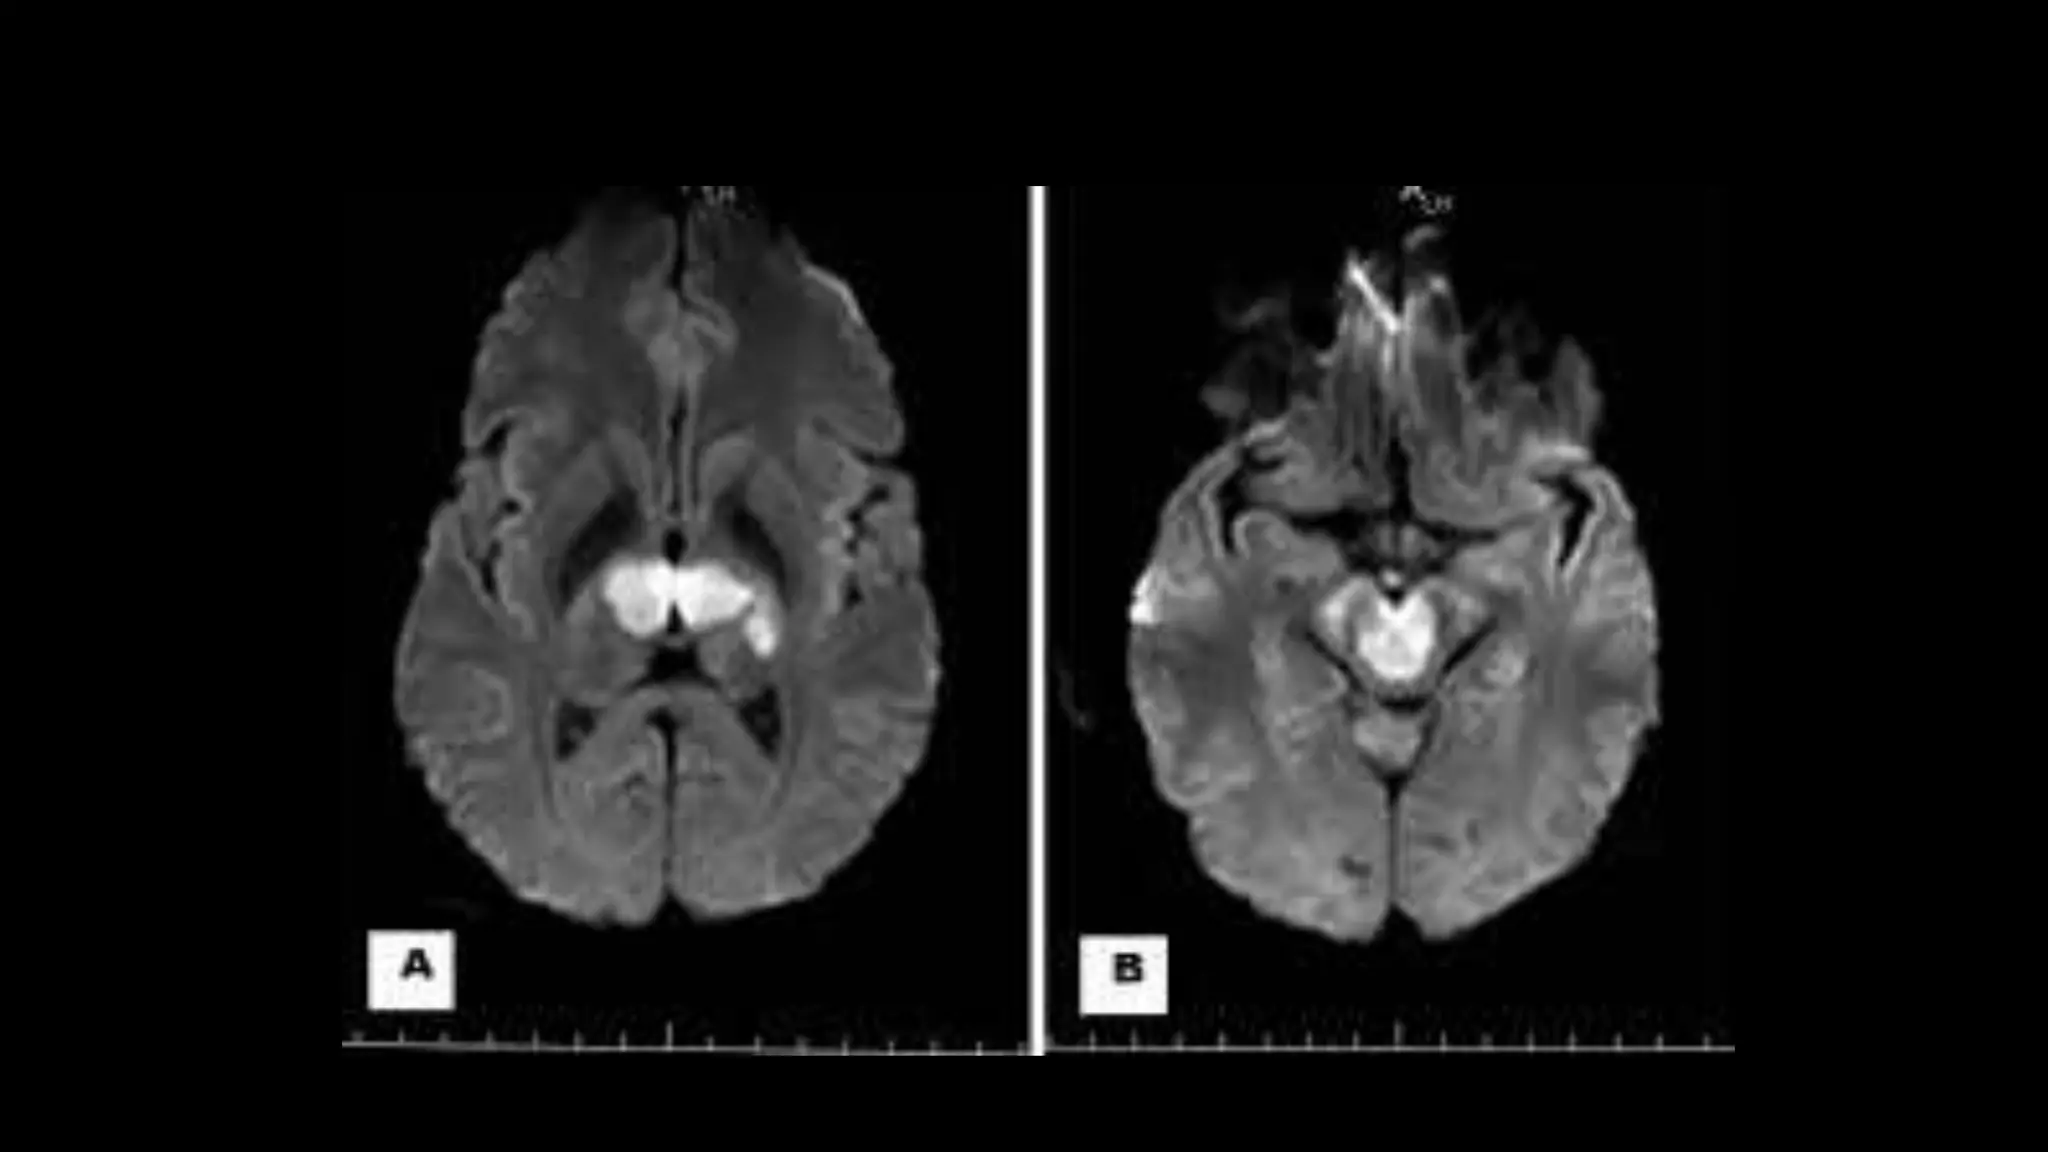

DEEPVENOUSTHROMBOSIS

IMAGING FEATURES

Thalamic edema is the imaging hallmark , may

extend to caudate region and deep white matter.

ICV

HEMORRHAGE IN

BOTH THALAMI

SS

ENGORGEMENT OF

MEDULLARY VEINS

VOG

BITHALAMIC EDEMA NON

VISUALIZATION

OF DEEP VENIS

• #151 Axial graphic depicts deep venous occlusion with thrombosis of ICV , VOG and hemorrhage in both the rthalamus. Note the engorgement of medullarty veins

• #152 AXIAL FLAIR image show extensive signal abnormalities within both thalaMI extending into caudate nuclei . Saggital 2d phase contrastt MR venogram shows no signal from the portion of deep venous system s/o thrombosis